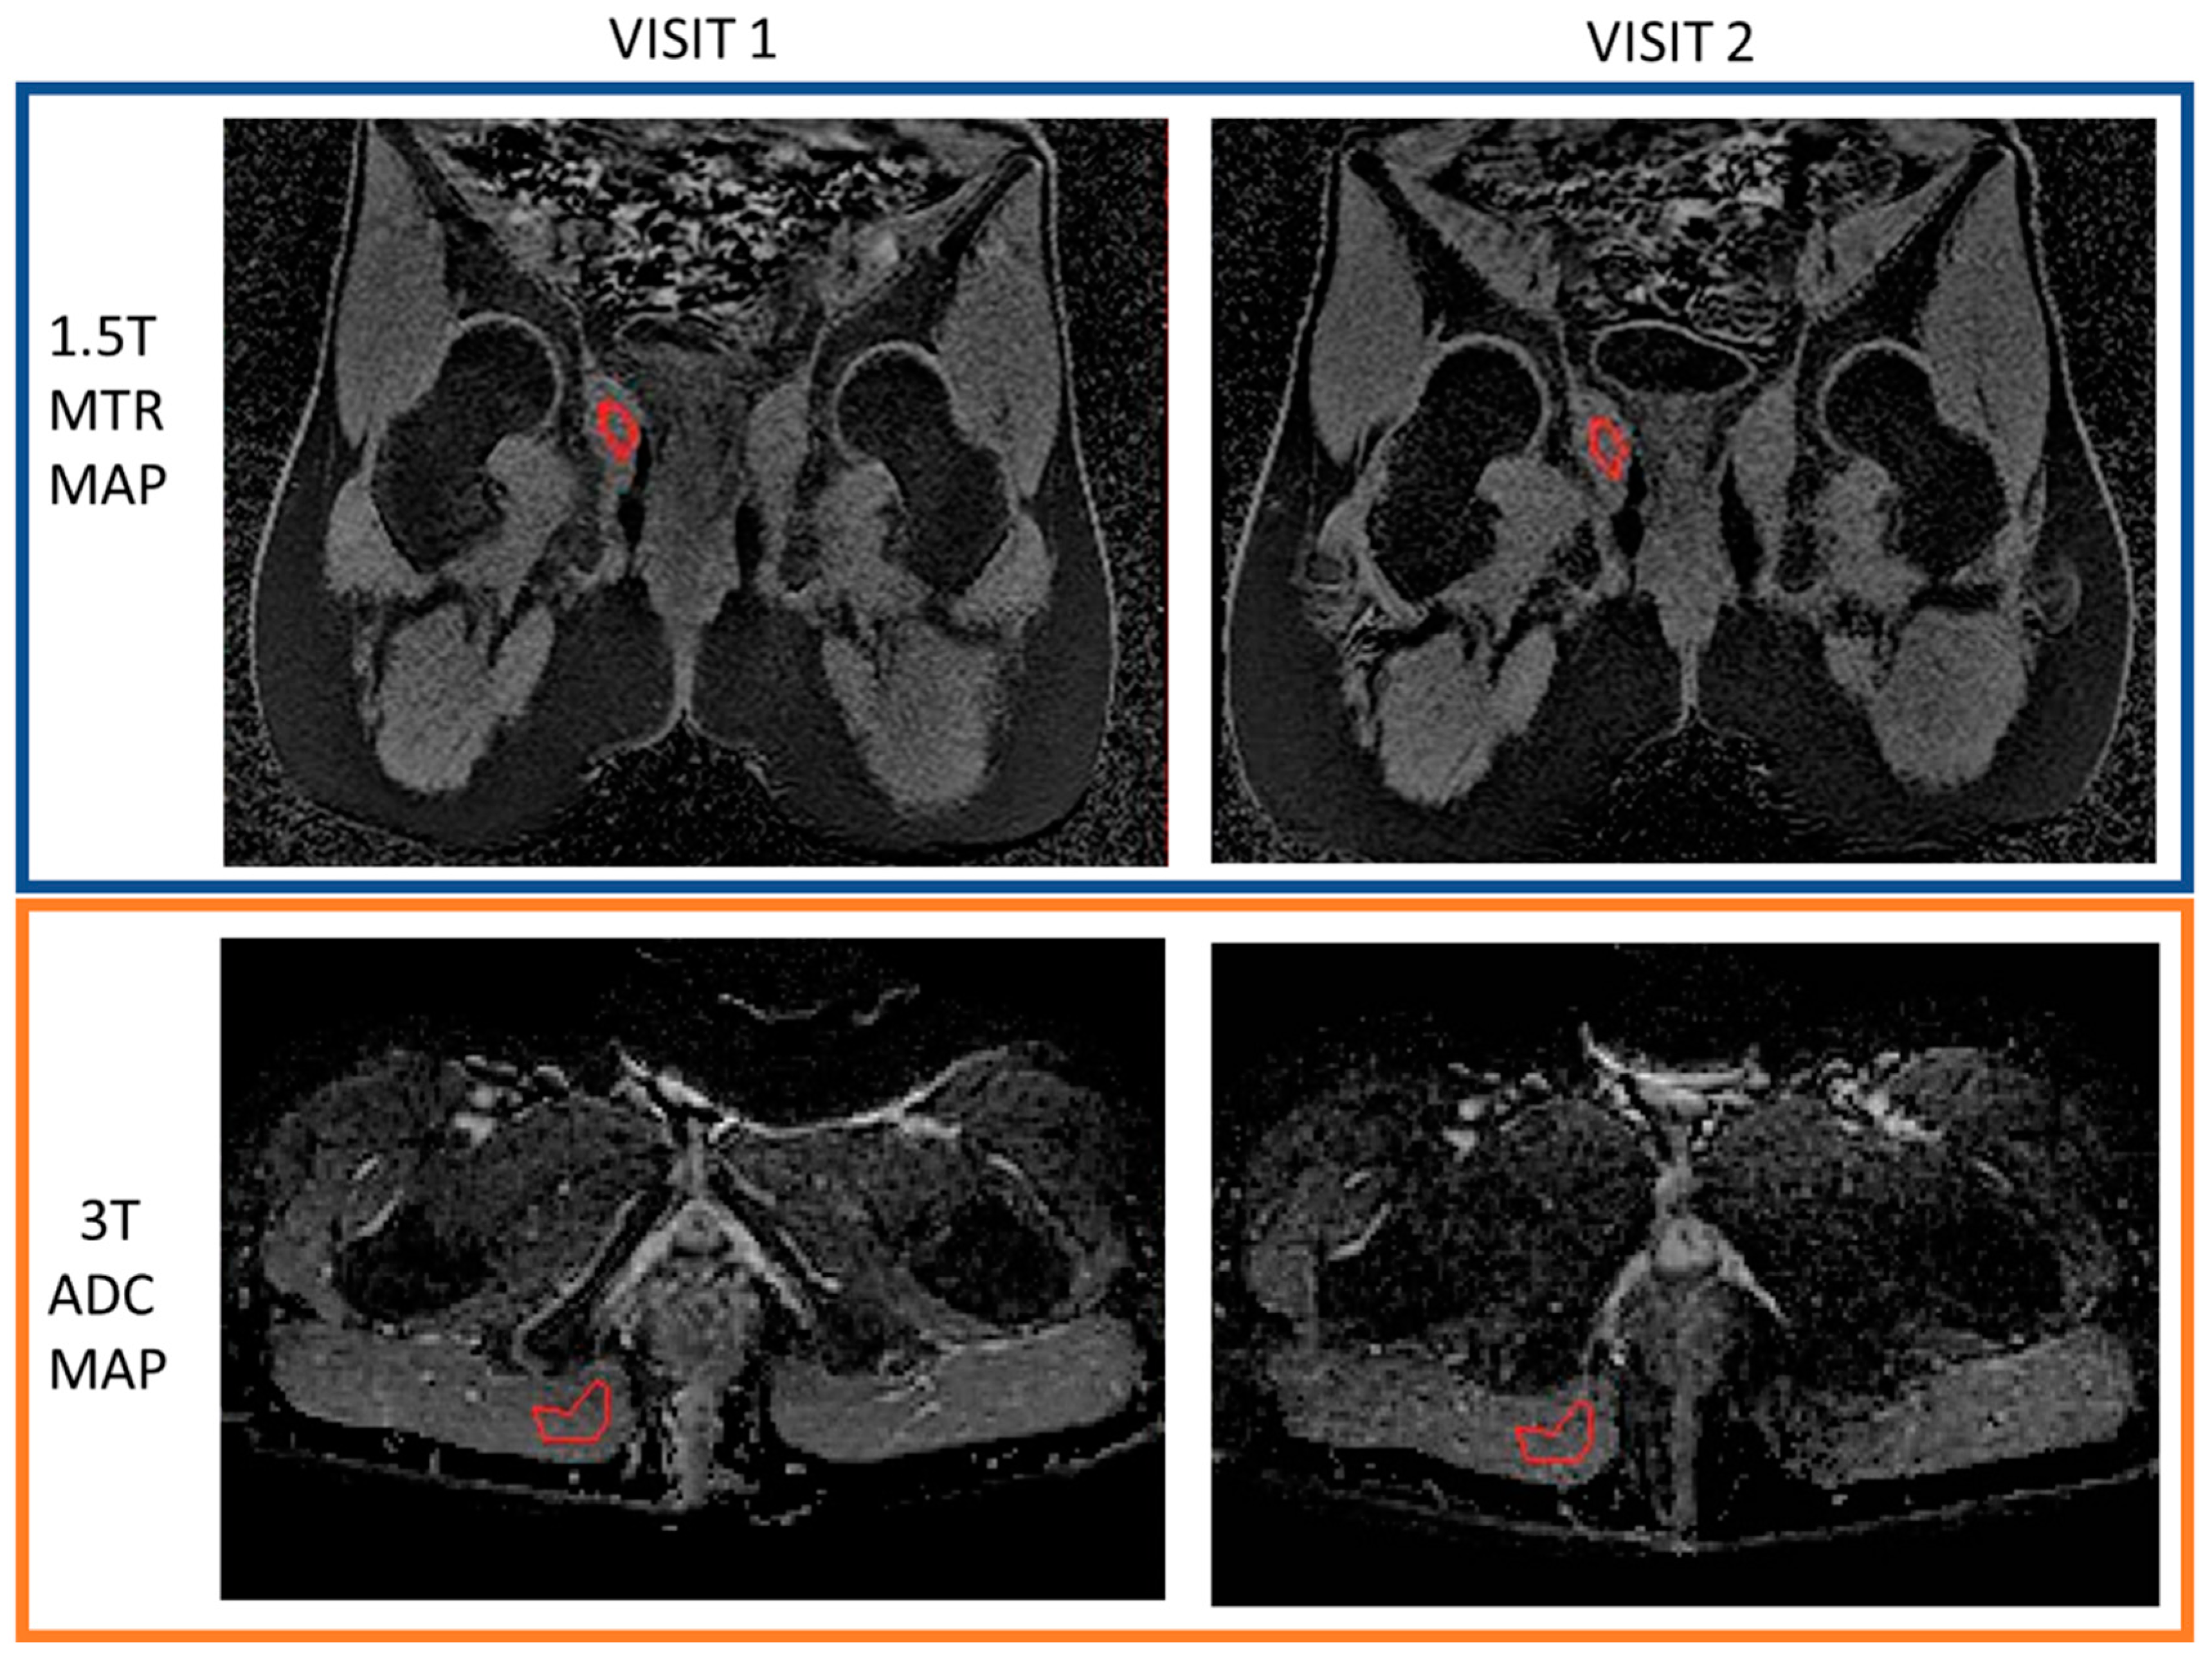

2.3.2. Repeatability of Quantitative Measurements

3.3. Repeatability of Quantitative Measurements